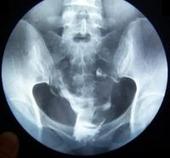

随着社会的高速发展,输卵管堵塞的发病率居高不下,成为了导致女性不孕的一大疾病。目前来说输卵管照影是检查诊断输卵管堵塞的高效方法,具有高效性、准确性、安全性等特点。输卵管造影已被临床广泛使用。输卵管照影诊断输卵管堵塞的优势在哪里?泉州玛丽医院的专家提到其优势主要有以下几点。

输卵管造影检查可清晰观察到输卵管堵塞的病灶及其相关局部的形态,对所有软组织及其活动情况均可全面了解,以达到准确判断输卵管的堵塞部位以及输卵管的内部功能,对后续的治疗提供一定指导,这是输卵管造影技术的一个主要优势。

输卵管造影检查是一种几乎无损伤、无并发症等副作用的安全诊断手段,在临床诊断输卵管堵塞的过程中,深受患者和医生的一致好评,这也是输卵管造影技术的一个优势。

输卵管造影检查几乎适用于所有输卵管堵塞的患者,尤其可明确诊断异物导致的输卵管堵塞,是优于其他诊断方法之处,可大大降低疾病的误诊率和漏诊率,这也是输卵管造影技术的一个较大优势。

输卵管造影检查不仅是一种疾病的诊断方法,还是一种辅助治疗方法,对输卵管堵塞患者引发的某些不孕症状具有一定治疗作用,这是输卵管造影技术的一个明显优势。